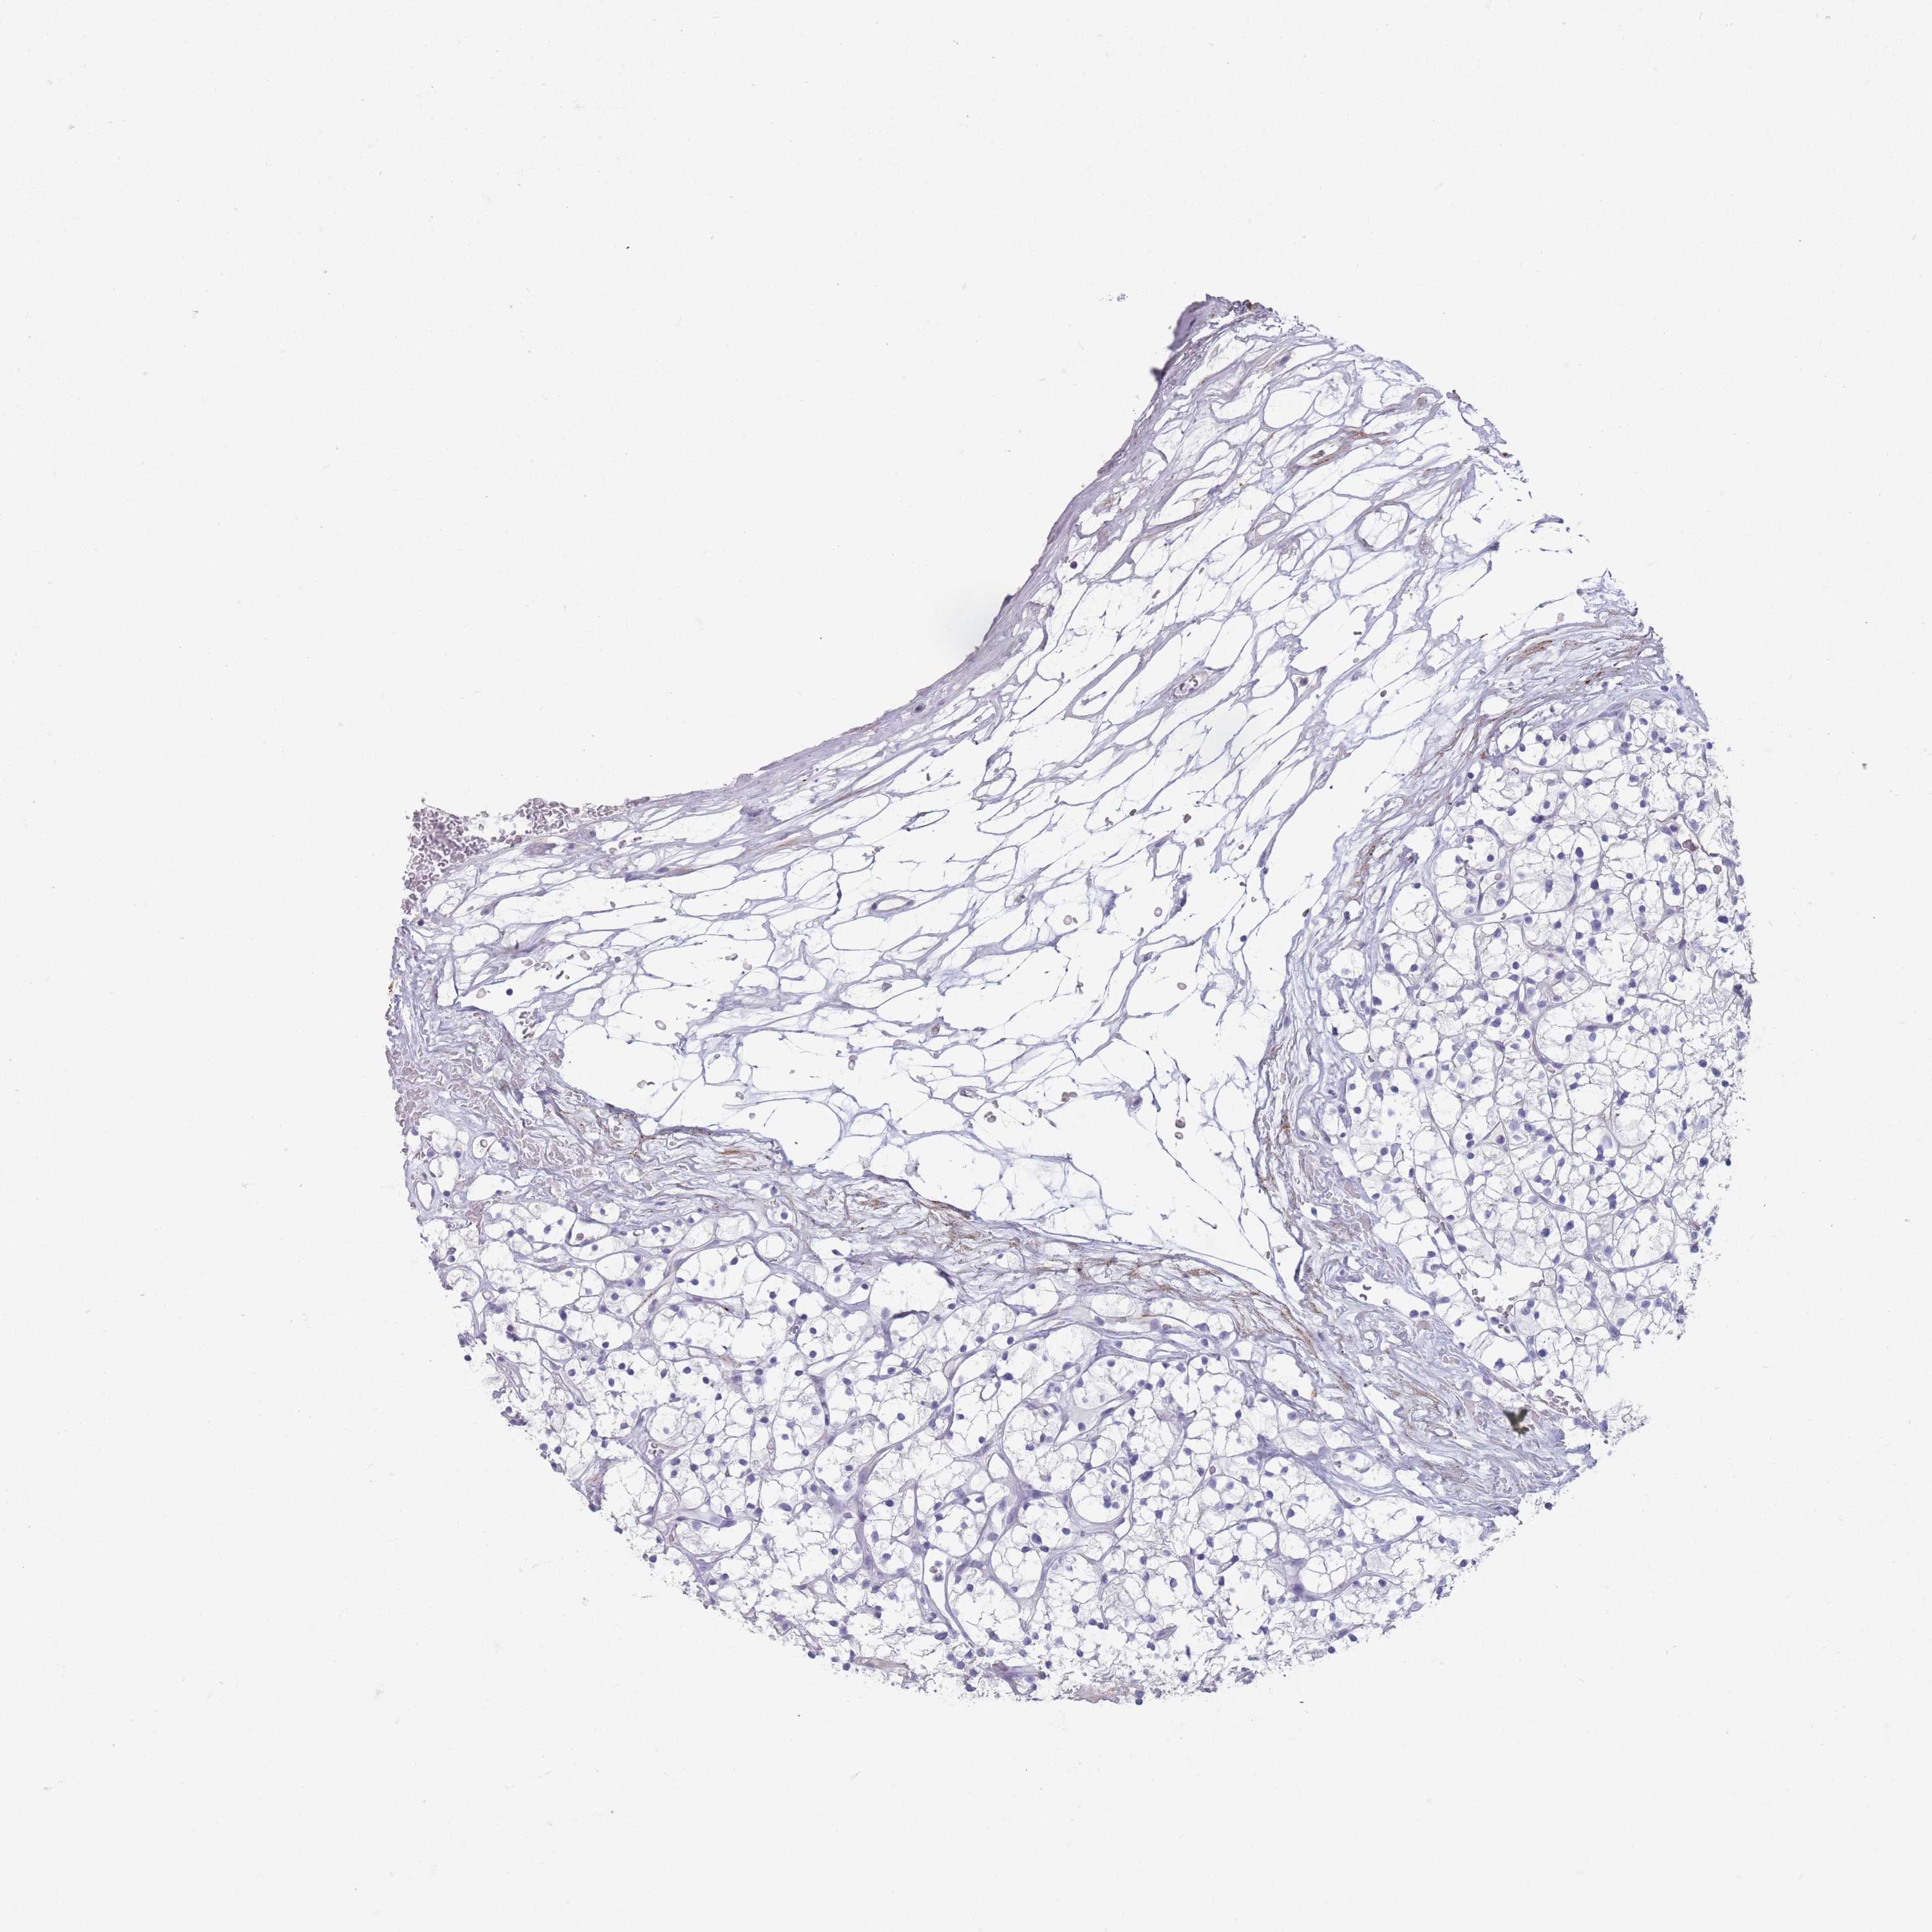

RNA-seq data is reported as average FPKM (number Fragments Per Kilobase of exon per Million reads), generated by the The Cancer Genome Atlas (TCGA) .

Normal distribution across the dataset is visualized with box plots, shown as median and 25th and 75th percentiles. Points are displayed as outliers if they are above or below 1.5 times the interquartile range. FPKM values of the individual samples are presented next to the box plot.

Average pTPM 0.0

Number of samples 100